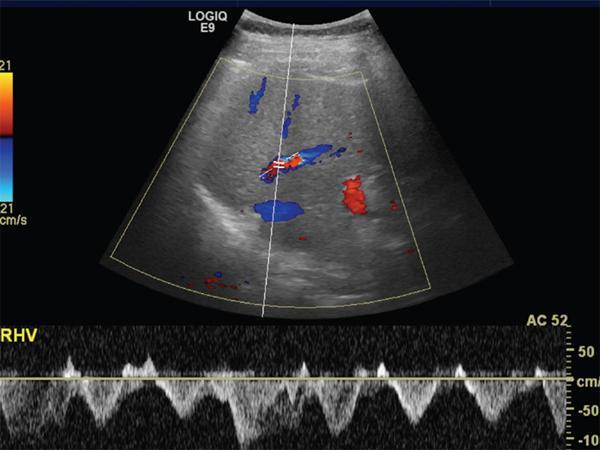

Imaging plays a significant role to make an early diagnosis and establish the best treatment options for posttransplant complications as clinical manifestations and laboratory parameters in many of the complications are usually nonspecific and overlapping. The imaging evaluation of postoperative complications remains the same in both types of liver transplants (DDLT and LDLT). Ultrasound with colour Doppler is usually the first modality of choice in the immediate postoperative period due to its easy and bed side availability with high accuracy and ability to pick up all major posttransplant complications, though it has a drawback of being operative dependent. It is usually part of regular postoperative assessment of the recipient for initial few postoperative days, playing an important role in picking up early complications. It is essential for the radiologist to know the details of the individual patient’s postoperative anatomy and surgical details, since anastomoses are the locations where complications occur most frequently. Goals of ultrasound evaluation in early postoperative period: Vascular evaluation with colour Doppler: CT/MRI imaging plays a supportive role for confirmation of the findings seen on ultrasound or colour Doppler or is done as an advanced imaging in case of mismatch between clinical or laboratory parameter and ultrasound or Doppler findings. MRI is particularly important for assessment of the biliary tree. First postoperative Doppler is done within 24 hours of the surgery and it serves as the baseline for comparison in the future. The haptic artery needs to be evaluated at the anastomotic site and also in the intrahepatic portions and the parameters to be evaluated are the systolic upstroke, PSV and resistive index (RI). Table 9.14.16 gives normal ranges of these parameters. Normal hepatic artery Doppler waveform demonstrates rapid systolic upstroke, with a systolic acceleration time (SAT) of less than 0.08 second and continuous diastolic flow, displayed above the baseline. A wide variability is observed in PSV of HA in the immediate postoperative period even in the absence of any hepatic arterial complication. Normal values may vary averagely from 40 to 120 cm/s. Vascular kinks or anastomotic site oedema in postoperative period can lead to falsely increased PSV in the HA. Correction of Doppler angle must be kept in mind while measuring the PSV of HA so that the angle aligns with the direction of the artery and must be less than 60 degrees to avoid inaccurate results. The hepatic arterial RI is an important tool to assess the hepatic arterial waveform in postliver transplant setting, as it allows semiquantitative estimation of the resistance to arterial flow into the liver. The normal RI ranges from 0.55 to 0.80 in posttransplant patients. The RI increases with decrease in the diastolic flow in the hepatic artery, which suggests increased resistance to the hepatic arterial flow. Absence or reversal of diastolic flow in the hepatic artery corresponds to an RI of 1.0 It is important to note that, increased RI of the hepatic artery (greater than 0.8) is a normal findings in the first few days after liver transplantation, due to decreased diastolic flow, which is attributed to allograft oedema, increased cold ischemia time, increased portal flow or vessel spasm. These transient arterial waveform abnormalities in early postoperative period usually resolve and normalize in 7–15 days on the follow-up Doppler studies. In view of significant variability in the PSV and RI of the hepatic artery in immediate postoperative period, other than in cases of absent arterial flow, the diagnosis of a hepatic arterial complication is seldom established on the basis of a single postoperative Doppler ultrasound. Arterial waveform abnormalities on the immediate postoperative scans should be followed closely and correlated with the patient’s clinical findings including liver function tests. Persistence of the abnormalities on serial follow-up Doppler studies or further deterioration of the waveform suggest presence of arterial complications. A decrease in hepatic arterial RI (RI < 0.55) is a more ominous finding than increased RI and is usually a concern for serious arterial complications like HA stenosis or impending thrombosis. The SAT – the interval from end-diastole to the first systolic peak – is a measure of the rapidity of the upstroke and normally should not exceed 0.08 seconds (Fig. 9.14.27). Portal vein evaluation needs to be done on greyscale ultrasound as well as on the colour Doppler. The presence of echogenic thrombus or filling defect is better appreciated on the greyscale ultrasound images. The PV peak velocity (measured at the anastomotic site) is the most important parameter for Doppler evaluation along with spectral waveform analysis. The normal portal vein flow after liver transplantation is hepatopetal, monophasic with respiratory plasticity (Fig. 9.14.28). The portal venous velocity is variable and tends to decrease on serial examinations after transplantation. During the early postoperative phase, turbulent flow with high velocities may be a normal finding which tend to decrease on serial examinations. Hepatic veins reveal a triphasic waveform (Fig. 9.14.29) due to transmission of cardiac pulsations. Though loss of triphasicity is seen in HV stenosis, it is a very nonspecific finding and biphasic or monophasic waveforms are often seen in normal posttransplant patients. Therefore, presence of hepatic venous triphasicity can exclude hepatic venous stenosis; however, loss of triphasicity does not imply presence of a hepatic venous complication. The terms early posttransplant complications is variably used in literature for period of first 1–3 months after the OLT. Table 9.14.17 summarizes post transplant complications in early and late post transplant period. Vascular complications are a common cause for allograft failure after hepatic transplantation. Early detection of the vascular complications is possible with the help of imaging, which can help reduce the incidence of graft failure. Table 9.14.18 below describes approximate timeline of various post transplant complications in post transplant period. Hepatic artery stenosis First three months Portal venous thrombosis Majority within four weeks Portal vein stenosis Usually late (>6 months) Hepatic venous stenosis Usually late (>6 months) Hepatic arterial complications are particularly significant in postliver transplant patients, as unlike native liver, the biliary tree of a transplant liver is entirely dependent on arterial blood from the hepatic artery. As a consequence, any hepatic arterial complication resulting in compromised hepatic arterial flow, particularly hepatic arterial thrombosis, has a devastating effect on the biliary epithelium, inducing ischemia resulting in biliary strictures, necrosis, abscesses and allograft failure. Hepatic artery complications include HAT, stenosis, and pseudoaneurysms. HAT is a common and the most catastrophic complication after orthotopic liver transplant, and it represents more than 50% of all arterial complications. According to the onset, HAT can be defined as early (within the first month) or late (later than one month). The incidence of early HAT is approximately 4%–12% in adults and 42% in children, and it is a major cause of graft loss (53.1%) and mortality (33.3%) in the early postoperative period. Thrombosis occurring after the first month or late HAT has a more insidious clinical course and is less devastating. Other than surgical technical causes like small calibre vessels or size discrepancy in the donor and recipient vessels, stenotic anastomosis, kinking; several nonsurgical causes have been described for HAT, which include ABO blood type incompatibility, increased cold ischemic time of the donor liver, acute rejection and sluggish flow through the hepatic artery. Initially, symptoms, signs and abnormal laboratory values are absent in early HAT, whereas reduced or absence of flow within the hepatic artery can be readily picked up by bedside Ultrasound and Colour Doppler evaluation (Table 9.14.19). Ultrasound is diagnostic in 92% of cases of HAT. Timely diagnosis of HAT allows for therapeutic interventions to restore the hepatic artery patency by vascular intervention or surgical reexploration to salvage the graft; if these measures fail retransplantation is needed in most cases. On Doppler ultrasound, acute HAT is diagnosed by: Graft oedema, systemic hypotension, and high-grade hepatic artery stenosis (HAS) can lead to false-positive sonographic diagnosis of HAT; whereas, false-negative sonographic findings may occur in presence of periportal arterial collateral formation in chronic thrombosis. CT or MRI with standard angiographic protocol are usually performed to confirm the diagnosis, which will reveal a complete cut off of the hepatic artery after the anastomosis (Fig. 9.14.30). Arterial anatomical variations like replaced recipient hepatic artery or any technical modifications used during arterial anastomosis need to be noted while reporting the angiography, which can guide the interventional radiologist in a better way. In late stages of HAT, hepatic arterial collaterals can develop. This collateral vessel flow can cause a dampened (tardus parvus) hepatic arterial waveform with a prolonged acceleration time (AT), similar to that seen in significant HAS. Presence of tardus parvus waveforms in the distal hepatic arteries is an ominous sign and must not be considered evidence of patency of the hepatic artery; it rather indicates the presence of either proximal stenosis or thrombosis. HAS has reported incidence of 5%–11% in posttransplant patients and is the second most common postliver transplant vascular complication. It usually occurs within 3 months of transplantation and most commonly involves the site of anastomosis. Risk factors for HAS are similar to those for HAT with few additional causes including clamp injury and intimal trauma from a perfusion catheter. If left untreated or undiagnosed, it can progress to HAT (Fig. 9.14.32) and related complications including hepatic ischemia, biliary complications, sepsis and ultimately graft loss. Treatment options aim at reestablishing adequate blood flow at the earliest either with angiographic intervention involving balloon angioplasty or stenting or with surgery if the previous measures are unsuccessful.